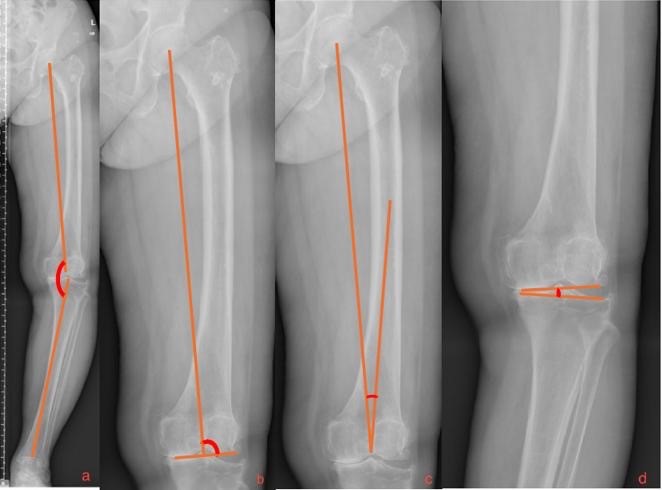

Purpose: Varus deformity is commonly observed in knee osteoarthritis (OA) and involves medial compartment degeneration, bone morphologic changes, soft tissue balance, and may complicate mechanical alignment during total knee arthroplasty (TKA), especially involving conventional alignment techniques. We evaluated the distribution of mechanical lateral distal femoral angle (mLDFA) and its association with coronal alignment parameters in Thai patients with varus knee OA to improve preoperative planning.

Methods: Patients with varus knee OA who underwent preoperative orthoroentgenographic imaging between 2020 and 2023 were retrospectively stratified into three mLDFA-based groups (<90° [A], 90° [B], >90° [C]) to compare differences in hip-knee-ankle angle (HKAA), joint line convergence angle (JLCA), and mechanically aligned-anatomical angle (MA-AA).

Results: mLDFA prevalence was determined in 444 patients (Group-wise: A=56.3%; B=28.7%; C=14.9%). Group A had smaller MA-AA values (5.38° ± 1.44°) compared with Group C (6.74° ± 1.69°, p < 0.001). Increased mLDFA values were associated with reduced HKAA values, while mLDFA values positively correlated with those of MA-AA. The mean JLCA value was significantly higher in patients with HKAA <170° compared with those with HKAA ≥170° (7.14° vs. 3.83°, p < 0.001). A JLCA value ≥10° was more prevalent in patients with HKAA <170° (18.2%) than in those with HKAA >170° (0.35%).

Conclusion: Increased mLDFA and MA-AA values were associated with more severe varus deformity (showed reduced HKAA values), indicating a need to individualize distal femoral valgus correction during TKA for patients with severe varus deformity. Preoperative mLDFA assessment may optimize alignment and surgical outcomes.